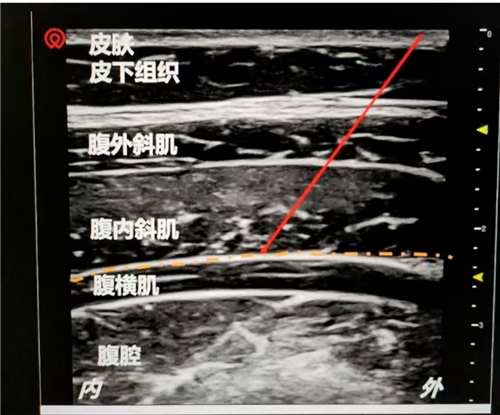

传统镇痛方式多以静脉或硬膜外给药为主,虽能一定程度减轻疼痛,但镇痛范围局限。 超声引导下TAP神经阻滞,是利用超声可视化技术,精准地将局部麻醉药注射到腹壁神经层,同时阻断了来自腹部切口和壁层腹膜的疼痛信号。因此,当进行术后按压宫底时,由按压牵拉所产生的主要疼痛通路被提前“关闭”,从而能极其有效地预防和减轻这一操作带来的剧烈疼痛,极大提升了产妇的术后舒适度。